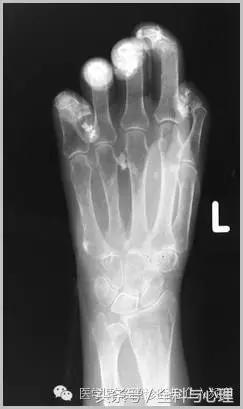

4、痛风石

为尿酸盐沉积形成,发生在关节周围软组织、包括韧带、肌腱、滑囊,眼、耳、鼻、喉、皮肤, 50%的钙化为X线平片可见。

痛风石,可见软组织肿胀及钙化灶。